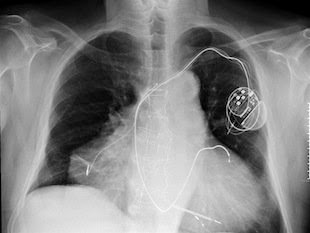

Bradley Cooper revealed his shocking nipples on the Ellen in 2012. He has a third nipple underneath his regular one, one on his arm and one on his leg!10. The man with two hearts.

A man in Italy was born with two hearts. He survived a double heart attack in 2010.11. The three legged man with two hearts.